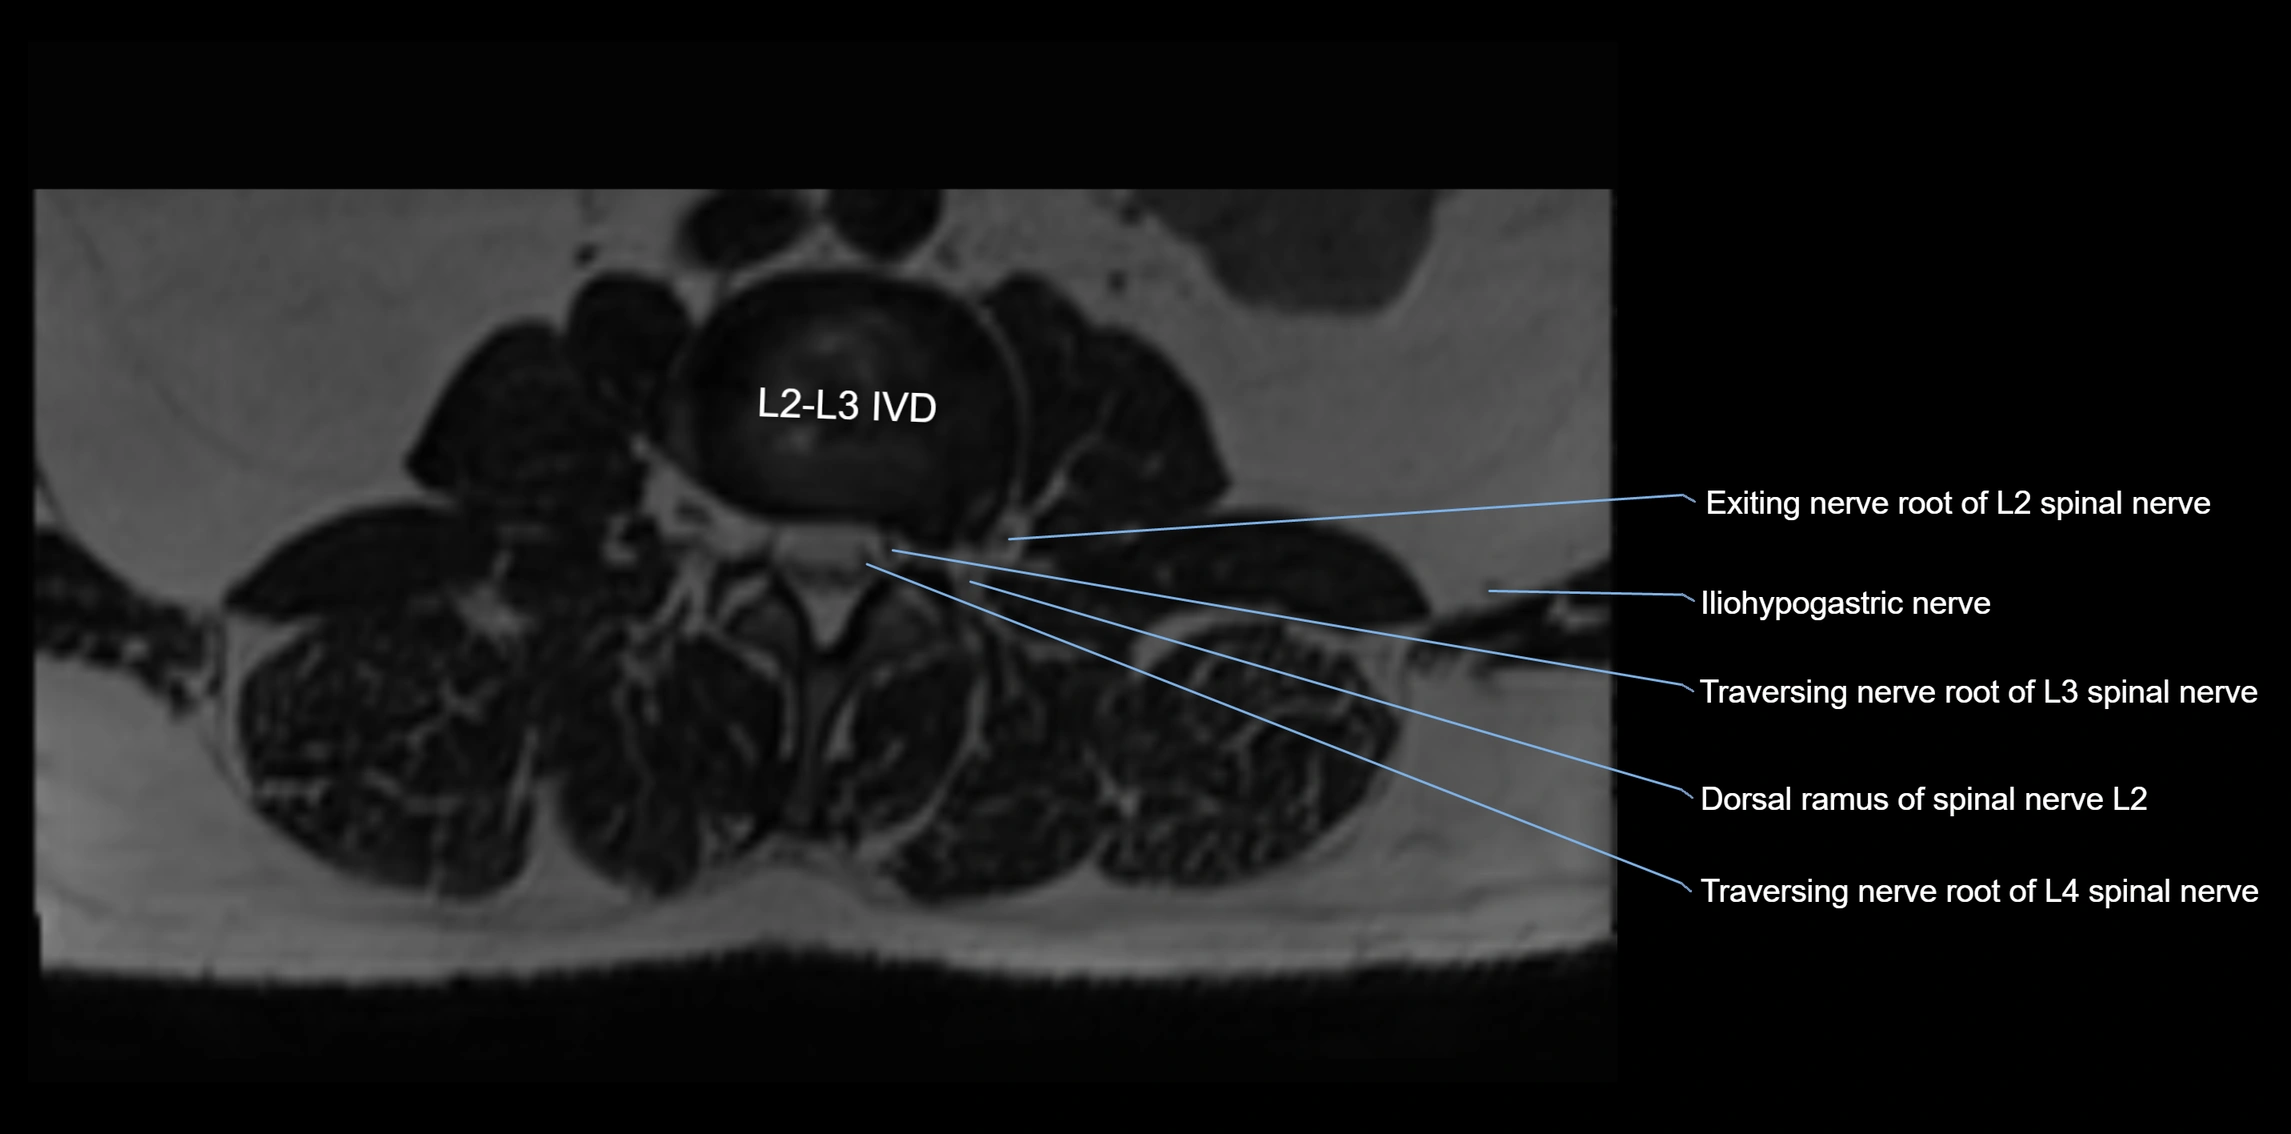

MRI Appearance

T1-weighted images:

• Nerve appears as a very thin low-to-intermediate signal intensity structure

• Surrounded by bright fat, aiding visualization

T2-weighted images:

• Nerve shows intermediate to mildly hyperintense signal compared to muscle

• Pathological involvement appears brighter

STIR (Short Tau Inversion Recovery):

• Normal nerve appears dark

• Inflamed or entrapped nerve appears bright hyperintense

T1 Fat-Sat Post-Contrast:

• Normal nerve enhances minimally

• Pathologic nerve (neuritis, entrapment, tumor infiltration) shows focal or diffuse enhancement

3D T2 SPACE / CISS:

• Nerve appears intermediate to mildly hyperintense compared to muscle

• Surrounded by bright fat or CSF, improving visualization

• Best sequence for mapping small pelvic nerves such as the anococcygeal